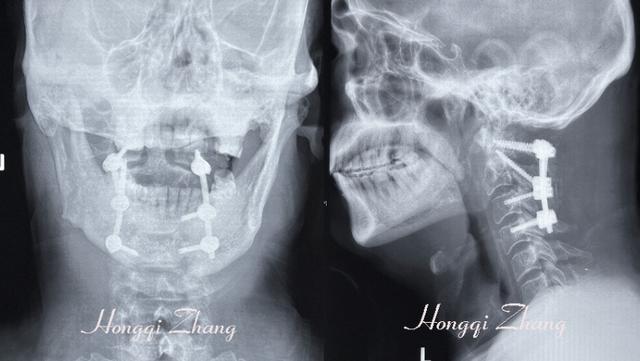

▲术后X示:环枢椎“△”固定位置满意,脱位完全复位。

2024年8月23日进行,手术由张宏其教授主刀,他凭借多年的临床经验和精湛的技艺,在唐明星副教授、高琪乐副教授、杨冠腾博士后、向刚博士的配合下,手术严格按术前计划进行并成功完成术。

手术过程中,张教授成功的运用普通的颈椎后路实心椎弓根螺钉作为Magerl技术的关节突螺钉,既完美解决了没空心螺钉的问题,而且该钉能与环椎椎弓根螺钉实现完整的钉棒连接,使得这些钉棒在环枢融合节段内形成了三角形结构,为患儿的环枢椎提供了非常稳固的支撑。手术仅耗时不到2小时,出血量100ml,手术效果令人满意。